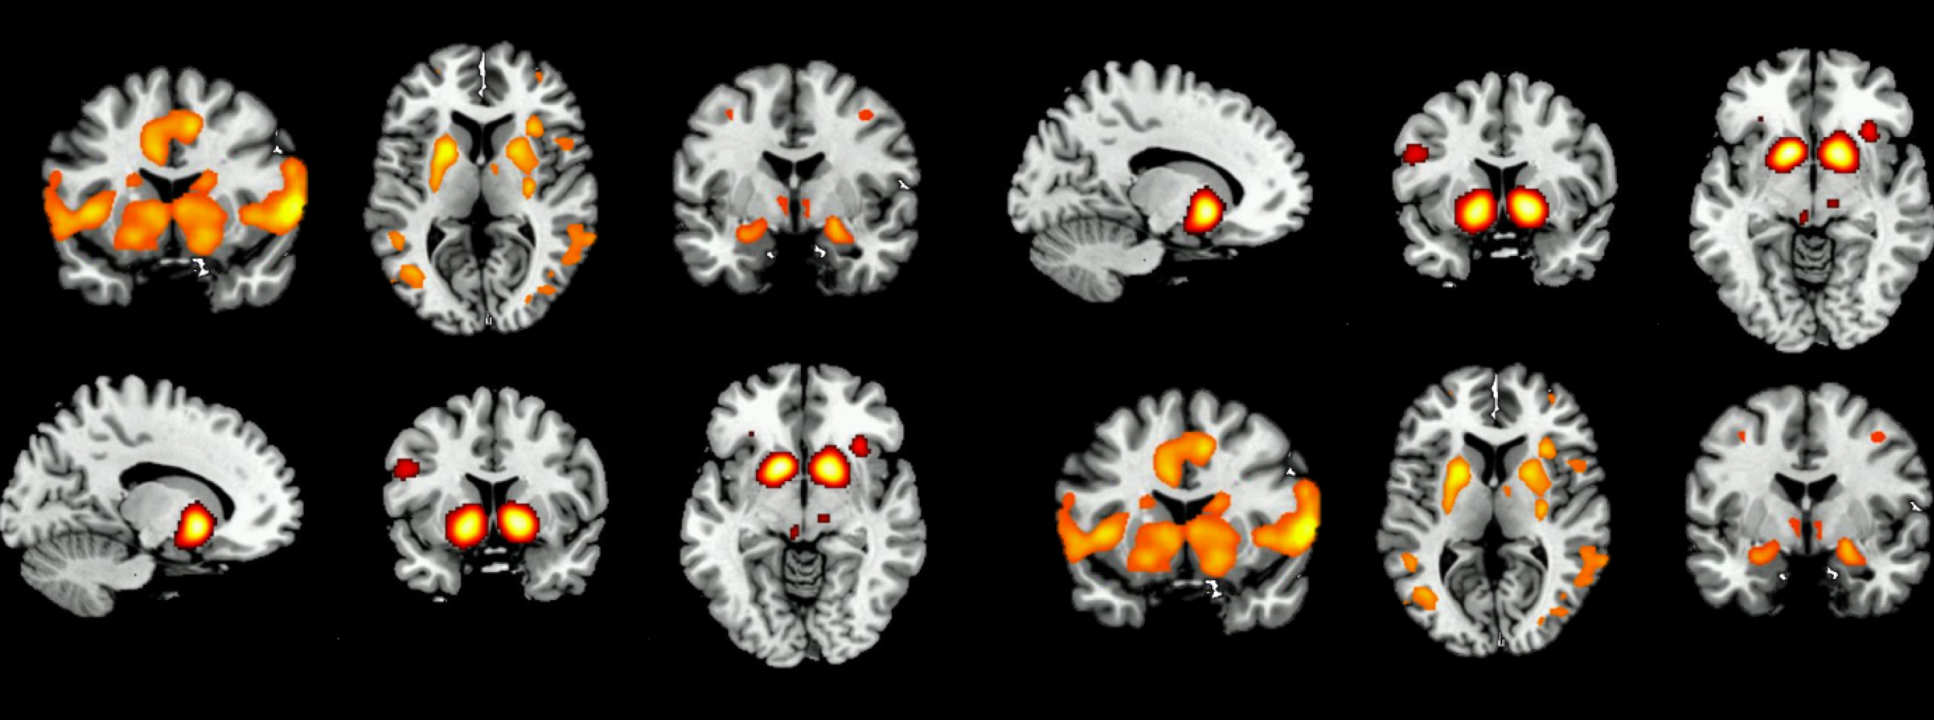

In this study, we are investigating the effects of opioid dependence on brain function, with the aim of improving treatment for detoxification and relapse prevention.

Our research uses brain-imaging techniques to detect subtle changes in brain function while performing psychological tasks. These tasks measure brain processes that are important in opioid dependence. We will investigate the effects of aprepitant (for further information, please see Aprepitant Information (.pdf)) on brain function in opioid-dependent individuals during methadone treatment, and again, after achieving abstinence from methadone.